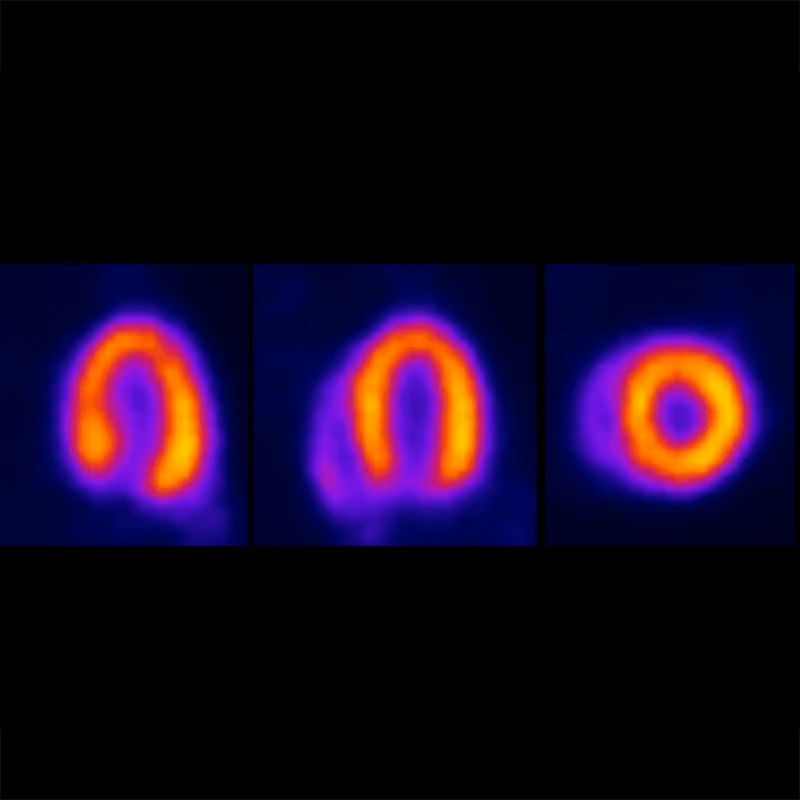

心脏门控成像

出色的心脏门控图像质量,适用于心脏功能分析。

〉动物:18克小鼠

〉示踪剂:13.3 MBq (360 μCi) ¹⁸F-FDG

〉采集:心电图门控PET,8帧

〉采集时间:90分钟